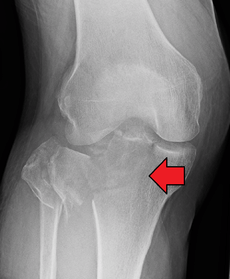

Lipohemarthrosis (presence of fat and blood from bone marrow in the joint space after an intraarticular fracture) seen on X-ray in a person with a subtle tibial plateau fracture

Lipohemarthrosis due to a tibial plateau fracture

Subtle tibial plateau fracture on an AP X ray of the knee

Lipohemarthrosis due to a tibial plateau fracture- A tibial plateau fracture seen on X-ray